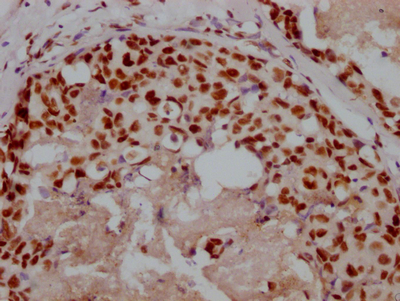

Western blot analysis of 1) C2C12 Cell Lysate, 2)PC12 Cell Lysate, 3) Hela Cell Lysate using HSP40 Rabbit pAb diluted at 1:1000.